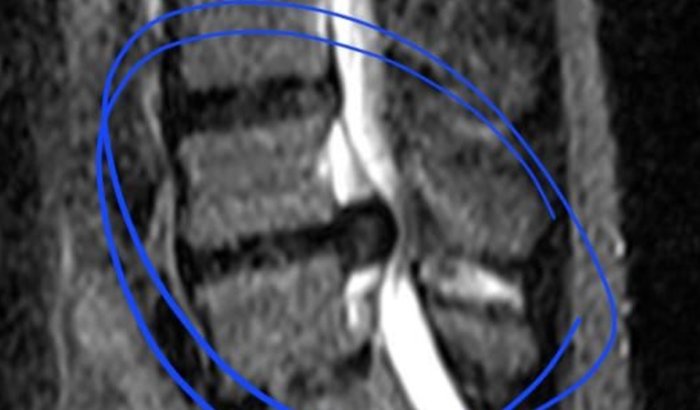

Tudo começou ainda na gravidez da minha esposa, quando o eu comecei com uma dor ciática. Com o tempo, essa dor evoluiu para um problema grave na coluna. Mesmo sentindo muita dor, continuei trabalhando todos os dias.

Tentamos vários tratamentos, fizemos exames e demos entrada pelo SUS. Aguardei 8 meses apenas para conseguir passar pela consulta. Quando finalmente fui atendido, o médico informou que o caso já estava grave e que não deveria ter esperado tanto tempo.

Hoje estou na fila da cirurgia pelo Estado, mas não há previsão de quando serei chamado. E infelizmente o quadro está piorando.

Já comecei a sentir formigamento no pé, não consigo segurar nosso bebê no colo e faz semanas que não consigo trabalhar por causa da dor.

Os médicos foram claros: não dá mais para esperar. Se houver mais demora, posso perder movimentos da perna.